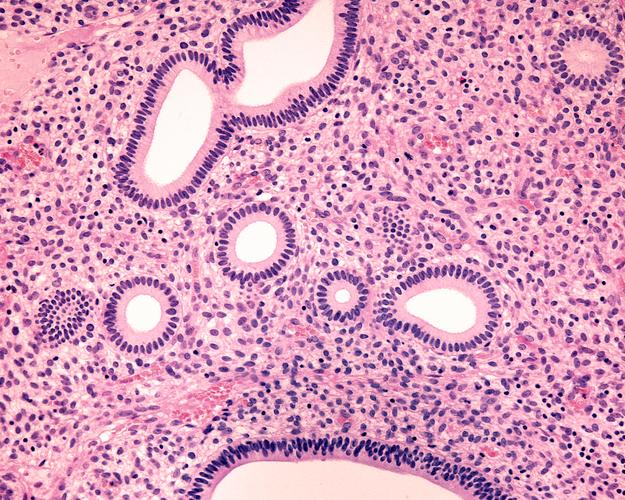

妇科疾病可分为炎症性疾病、内分泌疾病、肿瘤性疾病及妊娠相关疾病四大类,炎症性疾病如阴道炎、宫颈炎、盆腔炎等,多表现为白带异常、外阴瘙痒、下腹疼痛等症状;内分泌疾病如多囊卵巢综合征、月经不调等,常伴随月经周期紊乱、痤疮、不孕等问题;子宫肌瘤、卵巢囊肿等肿瘤性疾病则可能导致月经量增多、压迫感或腹部包块;妊娠相关疾病如异位妊娠、妊娠期糖尿病等,需通过定期产检及时监测。